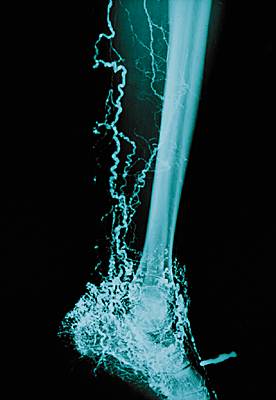

lymphographie

Examen radiologique des vaisseaux et des ganglions lymphatiques de l'abdomen après injection d'un produit de contraste iodé.